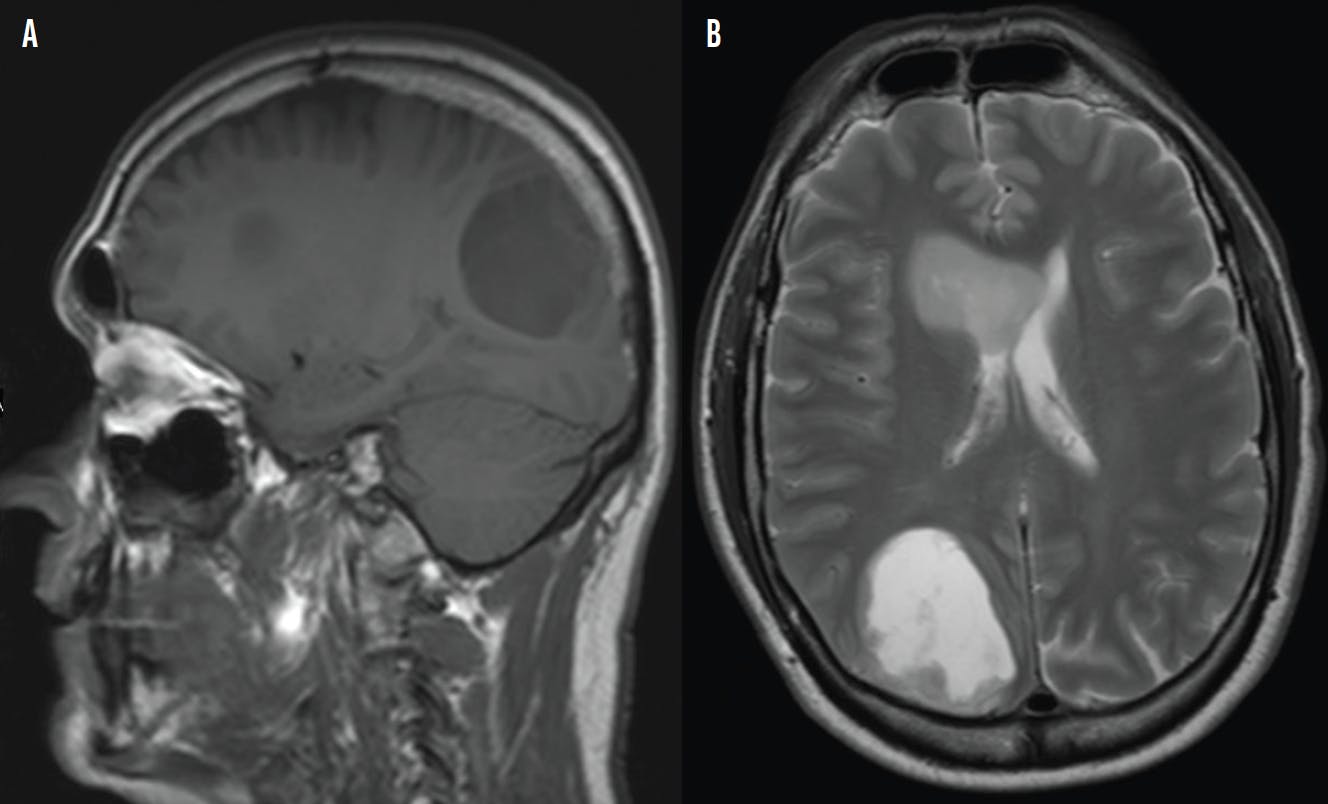

Given the presence of visual field defects with the patient’s neurologic symptoms, I immediately referred him to urgent care and neurology for imaging and evaluation to rule out stroke or a space-occupying lesion. A CT scan of his head was performed, which showed a cystic and solid lesion of the right cerebral hemisphere. An MRI of the brain with and without contrast was ordered for further evaluation. The MRI images showed a large, enhancing cystic lesion in the right parietal lobe and a solid, nonenhancing lesion in the right frontal white matter (Figure 2). Differential diagnoses included lymphoma, tumefactive multiple sclerosis, multifocal glioma, and metastasis. A PET scan was performed to rule out malignancy and metastasis.